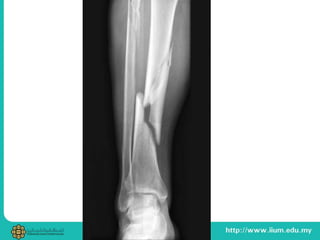

STRESS FRACTURE

• Occur in normal bone of healthy patient

due to repetitive stress below yield strength

• During repetitive strenuous physical activity

causing imbalance in Wolf's Law

• Tibial shaft, calcaneum, MT, NOF

• Pain after – during – without exercise

• Occur innormal bone of healthy patient due to repetitive stress below yield strength • During repetitive strenuous physical activity causing imbalance in Wolf's Law • Tibial shaft, calcaneum, MT, NOF • Pain after – during – without exercise